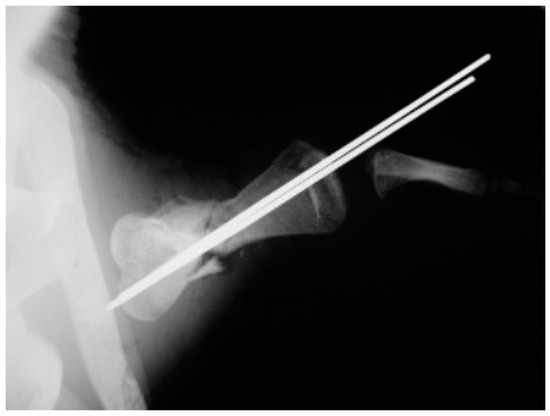

A juvenile sea turtle was presented to the Sea Turtle Clinic (STC) of Veterinary Medicine Department of the University of Bari with an entanglement lesion affecting the right front flipper. On admission, the sea turtle was measured and underwent a complete physical examination; curved carapace length (CCL) from notch to tip ranged 41 cm, curved carapace width (CCW) was 37 cm, and the weight was 18 Kg. The turtle appeared responsive but weak and dehydrated. Clinical evaluation of the musculoskeletal system performed out of the water showed swelling of the right front flipper and evidence of pain on deep palpation of the respective brachial muscle. A reduction in the right front flipper’s range of motion was observed when the turtle was examined in the water. Radiographic assessment, in dorso-ventral (D-V) and Caudo-Cranial (C-C) projections, indicated detachment of the distal epiphysis of the humerus, compatible with a type II Salter-Harris fracture, together with a transverse diaphyseal fracture (Figure 1). The turtle underwent general anesthesia, and the craniodorsal access to the humeral diaphysis was performed. The epiphyseal fracture was reduced by closed surgery and fixed using two crossed 2.5 mm Kirschner pins, introduced backward from the distal stump and brought out through the hyperflexed humerus-radio-ulnar joint. The same pins used to fix the epiphyseal fracture were inserted into the proximal stump to fix the diaphyseal fracture. After checking the stability of the fractures reductions, the surgically sectioned soft tissues were reconstructed, and post-operative radiographs were performed. Follow-up was performed after the surgery at 2, 4, 12, 16, and 24 months, when the turtle was released at sea. Three months after its release at sea, the turtle was caught dead in a fishing net at a depth of 40 m. To determine the evolution of bone repair from turtle release to death, the right humerus was removed for histological and histomorphometry analyses. Immediately after explant, the humerus was fixed in 4% buffered paraformaldehyde, dehydrated in ethanol, and embedded in methylmetacrylate. Serial cross sections, 750 µm thick, were cut at both the diaphyseal and epiphyseal fracture gaps using a circular diamond-bladed saw (Gillings Hamco) and were ground to a thickness of 100 µm. Sections were placed on a specimen holder and microradiographed using a microradiograph (Constant 1-K, Ital Structures, Italy) at a prefixed distance from the X- ray generator of 9.5 cm. X-ray exposure was set up at 8 kV and 14 mA. Contact microradiographs were obtained on Kodak high-resolution film (SO 343, Eastman Kodak Co., Rochester, NY, USA), developed with Kodak HC-110, fixed in Kodak UNIFIX, washed in distilled water and then airdried at room temperature. Sections were subsequently stained with 1% toluidine blue (pH 3.7) for mineralized tissue. Four separate levels were selected, three belonging to the mid-diaphyseal fracture gap, and one level to the epiphyseal fracture gap: the first and the fourth levels corresponded to the proximal and distal part of the callus, respectively, and the second and third levels to the center of the fracture (Figure 2). As a control, the left humerus, which had never been fractured, was processed with the same procedure. On the stained sections, using a Nikon DS-5 camera connected to a stereomicroscope (SMZ800, Nikon Europe B.V., Amstelveen, The Netherlands) and a DS camera control unit, the callus extension was measured and the amount of new laid down bone, cartilage, and fibrous tissue, expressed as percentage ratio of the entire section, were evaluated. Histomorphometry was performed using Nis-Elements BR analysis software (Nikon Europe B.V.).

The post-operative radiographic examination confirmed the correct reduction of the diaphyseal fracture, bone realignment, and the good fixation of the detached distal epiphyseal stump (Figure 3). Fifty days later, the X-ray follow-up showed persistent stability of the joint and bone sclerosis, near the diaphyseal fracture site. After 70 days, the turtle could swim and move around comfortably; radiographic examination showed a better filling of the diaphyseal fracture line and almost complete repair of the epiphysis (Figure 4). Four months after surgery, the animal was in good general condition and had recovered the right front flipper’s normal function. Radiography showed a complete repair of the epiphyseal fracture and remodeling of the normal bone architecture, while the diaphyseal fracture still lacked unifying bone callus tissue (Figure 5). After one year, the flipper showed complete clinical recovery without signs of pain, and radiologically the fracture site was fixed, showing signs of remodeling of the fracture stumps, areas of thickened fibrous tissue, but still no appreciable unifying bone callus (Figure 6a). The good positioning and tightness of the means of fixation were radiologically confirmed, but the surrounding bone reabsorption and decalcification processes were evident. Removal of the intramedullary pins was deemed necessary. Radiograms performed after removal of the pins showed the presence of calcified sites within the tissue interposed between the two bone stumps (Figure 6b). Two years after the procedure, radiographic follow-up demonstrated a better filling of the fracture line and further remodeling of the stump margins (Figure 7).

Figure 6. Radiographic examination at 12 months before (a) and after (b) removal of the synthesis methods (Caudocranial view): remodeling of fracture stumps, areas of thickened fibrous tissue, but still no appreciable unifying callus.